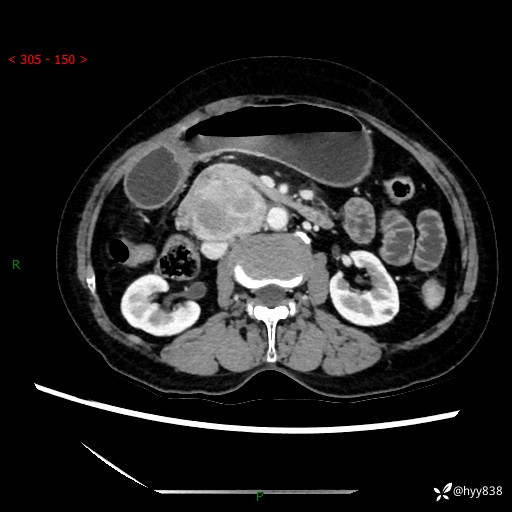

71岁/女,腹痛1月余。腹膜后肿物,间质瘤 VS 副节瘤 VS 平滑肌肉瘤---(有结果)

【患者信息】:71岁/女

【主诉】:腹痛1月余

【检查】:腹部CT增强扫描(外院CT平扫)